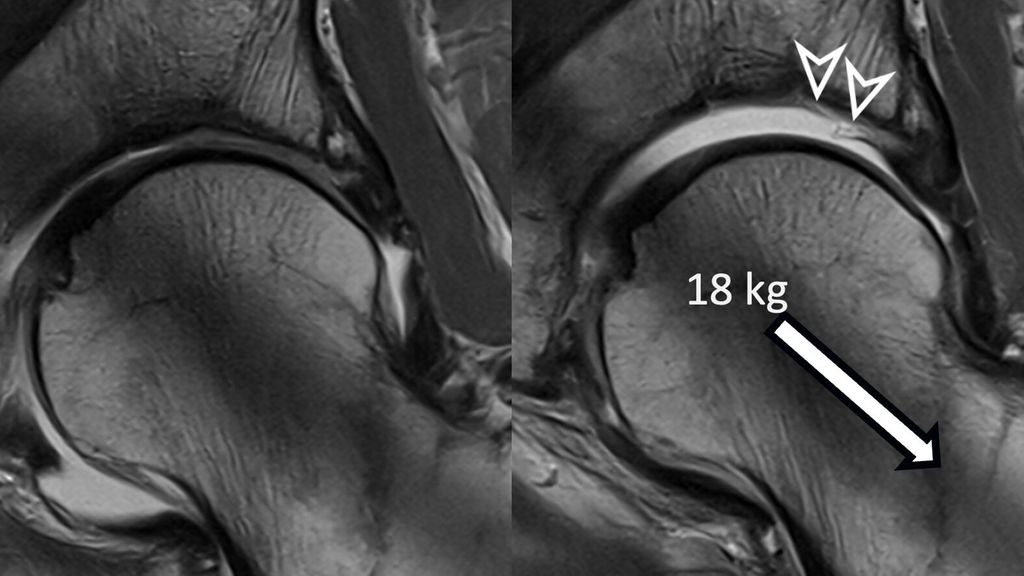

Fig. 1: Traction MR arthrography allows for better visualization of the opposing acetabular and

To improve visualization of the central joint cavity during MR arthrography, axial leg traction can be applied, similar to the joint distraction needed during hip arthroscopy (Fig. 1). Traction MR arthrography of the hip has shown high accuracy in detecting chondrolabral lesions, ligamentum teres injuries, and intra-articular loose bodies and has demonstrated its value in predicting failure of FAI surgery.5–8 It is particularly helpful for better visualizing the extent of cartilage damage in older patients with mild radiographic joint degeneration and thus aid in surgical decision making. Traction MR arthrography can also detect unstable labral tears in patients with hip dysplasia and may aid in planning treatment for femoral head necrosis in young patients with early collapse and preserved joint space.4